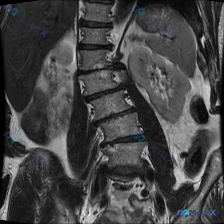

整理到一张腹部冠状位T2加权像的MRI资料,最初的焦点问题是“图中可以观察到什么?脊柱侧弯”。

先把影像里能看到的事实列出来:

- 肝、脾、双肾实质信号大致均匀,未见明显局灶性占位或梗阻扩张

- 腹膜后间隙清晰,无明显肿大淋巴结或积液

- 腰椎间盘T2像呈均匀高信号,提示水分含量尚好

- 确实能看到腰椎序列有轻微侧弯,但椎体形态在这个层面还算完整

📋答案:仅凭这张单一冠状位T2WI MRI,仅能确认“存在轻度腰椎侧弯”这一描述性事实;综合影像特征与风险分层,首先考虑良性/功能性脊柱排列异常,但必须警惕早期Modic改变/终板炎、隐匿性肿瘤/转移瘤等低概率高风险情况。